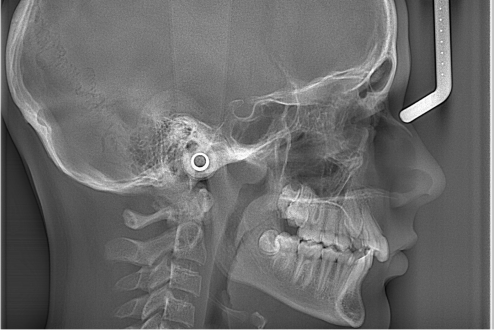

Телерентгенографія голови

Цей метод дозволяє отримати зображення черепа в прямій або боковій проєкції, що, в свою чергу, дає змогу лікарю дослідити будову зубощелепного апарату, виявити порушення і прогнозувати ефективність лікування на кожному з його етапів. Ці аналітичні дані (кефалометрія) необхідні для якісного ортодонтичного втручання.